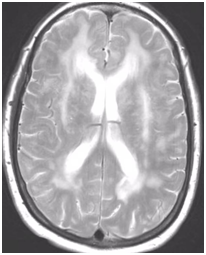

During follow-up in stroke clinic, her imaging was reviewed. MR imaging demonstrated large confluent areas of hyperintense T2 and FLAIR signal abnormality throughout the periventricular and deep white matter with extension into the subcortical white matter (Figure 1) (Figure 2). T1w images demonstrated low signal, corresponding to the T2/FLAIR abnormality on T2w images. This white matter abnormality is known as leukoaraiosis. The hyperintense T2/FLAIR signal abnormality also involved the anterior temporal lobes (Figure 3) (Figure 4) and external capsules (Figure 5) (Figure 6). This feature on MRI is uncharacteristic of other white matter diseases, notably the sporadic subcortical atherosclerotic encephalopathy. In our patient, the corpus callosum was spared. The lacunar infarcts were small vessel infarcts, typically seen in the deep white matter, basal ganglia, thalami, and the pons. On diffusion images, there was a small area of diffusion restriction in the left corona radiata that was consistent with an acute infarct (Figure 7) (Figure 8). Subsequently, there was an area of encephalomalacia on follow-up MRI at the location of the previous acute infarct. This abnormality correlated with the right-sided weakness seen prior to the index patient’s admission.

Figure 1 T2w axial image at the level of corona radiata demonstrates confluent hyperintense signal abnormality in the deep and subcortical cerebral white matter.